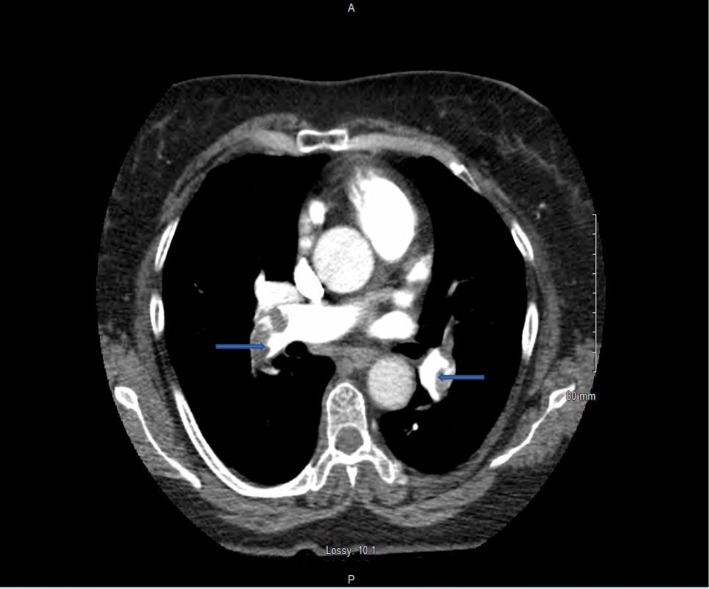

Fig. 1.

CT scan demonstrates regions of hyper-attenuation within the right main and left pulmonary arteries (arrowheads)